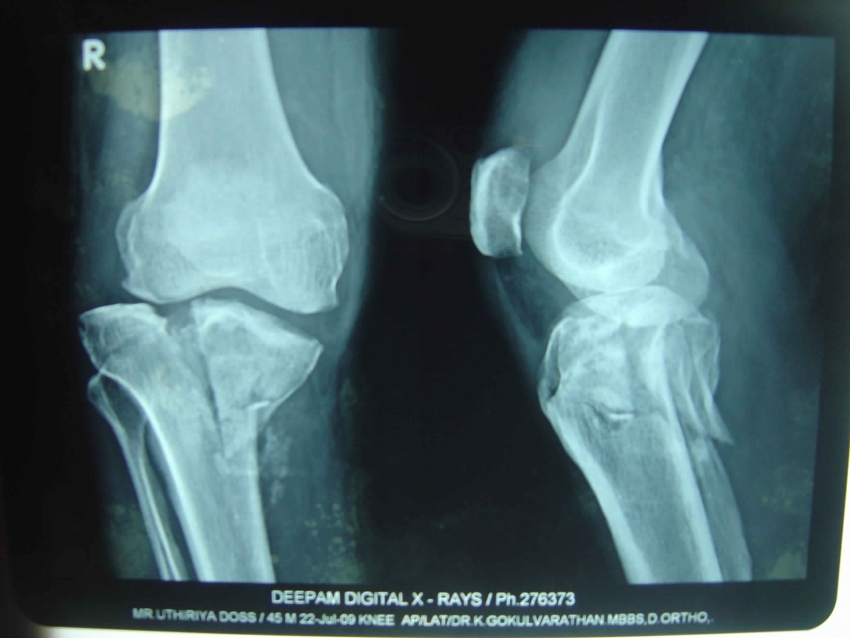

Impacted Fracture - एखादे हाड तुटते तेव्हा त्या हाडाचा हिस्सा दुसऱ्या हाडांमध्ये घुसण्याची स्थिती.

IntraArticular Fracture - हाडासोबतच सांध्याचा पृष्ठभाग सुद्धा फ्रॅक्चर होणे.